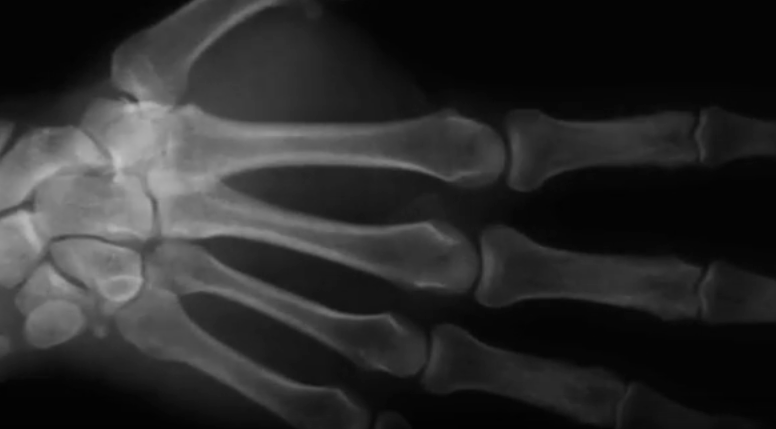

Ce se intampla cand iti pocnesti degetele, Foto: Captura YouTube

Oamenii de stiinta au folosit imagistica prin rezonanta magnetica (RMN) si investigatii cu ultrasunete pentru a intelege ce se intampla cu incheieturile mainilor atunci cand o persoana isi pocneste degetele, punand punct unei dezbateri vechi de cateva decenii pe acest subiect, scrie Washington Post.

In luna aprilie, cercetatorii de la Universitatea din Alberta au publicat o lucrare in care foloseau date obtinute cu ajutorul iunui RMN si spuneau ca sunetul este provocat de spargerea bulelor de aer care se formeaza in lichidul ce inconjoara incheieturile – numit lichid sinovial.

O noua echipa de cercetatori a decis sa recurga la investigatii cu ultrasunete, care pot inregistra ce se intampla in corpul uman cu o viteza de 100 de ori mai mare decat cea a unui RMN.

Cercetatorii suspecteaza ca pocnetul si explozia luminoasa sunt lgate de schimbarea de presiune cares e produce in lichidul sinovial.